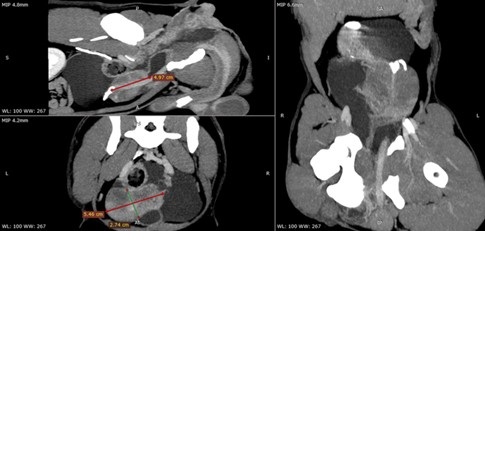

Se describe el caso de un canino adulto joven, macho sin esterilizar, que presentaba signos clínicos compatibles con una hernia perineal (tenesmo, constipación, deformación en más del periné, etc). El paciente fue evaluado mediante ecografía abdominal, donde se detectaron estructuras quísticas de gran tamaño asociadas a la próstata, las cuales desplazaban los órganos abdominales. Antes de proceder a la resolución quirúrgica, se realizó una evaluación tomográfica para delimitar con mayor precisión las estructuras afectadas. Durante el procedimiento quirúrgico, se abordaron las lesiones quísticas, realizando una omentalización del tejido residual. Además, se efectuó la fijación del colon y la vejiga a la pared abdominal, sin necesidad de intervenir el diafragma pélvico. Cultivo negativo y la histopatología compatible con una estructura quística. La recuperación fue sin complicaciones hasta la fecha del reporte, más de 12 meses. Este reporte tiene como objetivo resaltar la importancia de las evaluaciones prequirúrgicas imagenológicas, la complementación de estas y la relevancia de técnicas quirúrgicas como la omentalización de la próstata, junto con la fijación del colon y la vejiga, para un manejo integral y efectivo en este tipo de casos